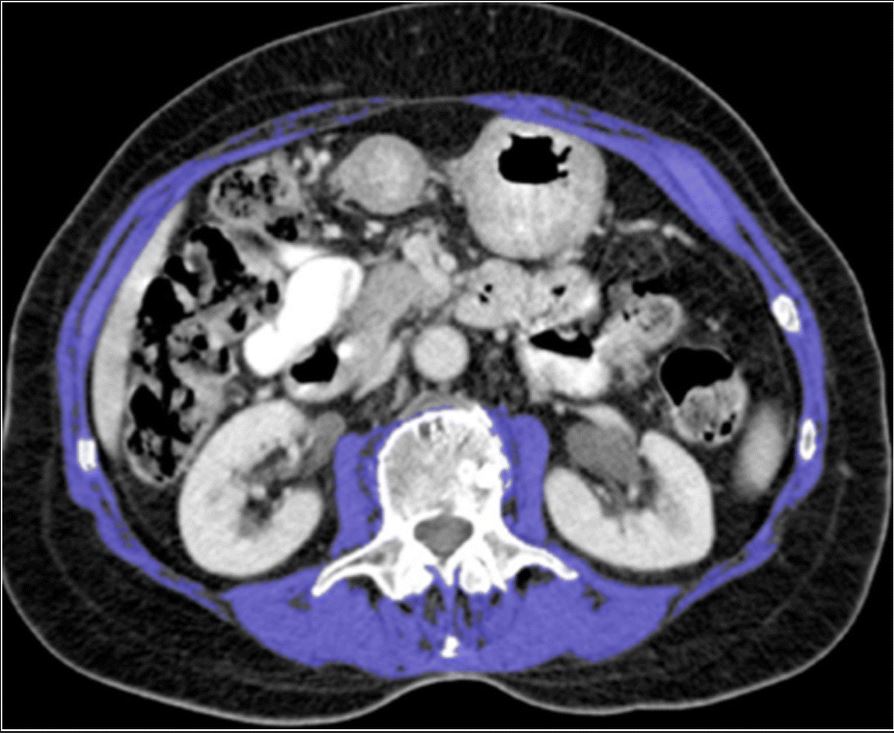

Any impact of sarcopenia and myosteatosis on postoperative outcomes in inflammatory bowel disease?

The goal of this retrospective analysis was to investigate outcomes in inflammatory bowel disease (IBD) patients who underwent surgical resection in relation to the presence of sarcopenia and myosteatosis. The authors determined that sarcopenia and myosteatosis in IBD were not associated with clinically relevant postoperative complications.